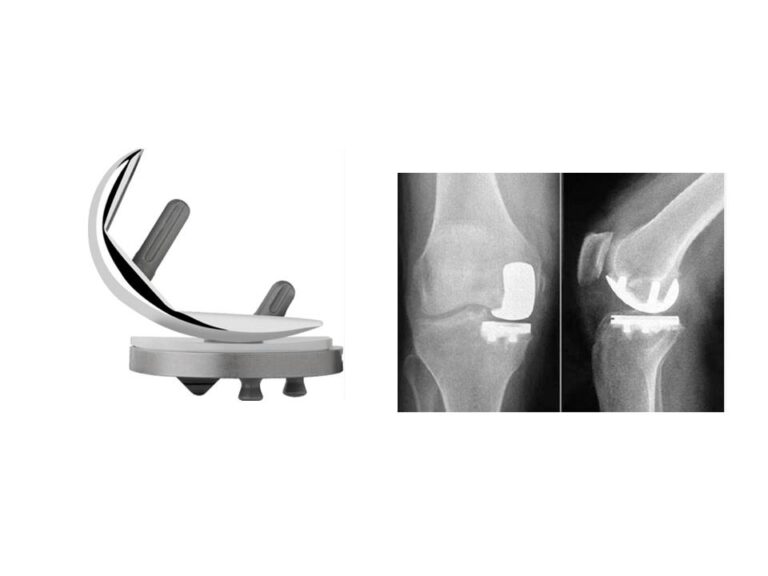

A Surgical Series of Unfortunate Events

A Surgical Series of Unfortunate Events Primary Total Knee Replacement Complicated by Intraoperative Medial Femoral Condyle Fracture “Good judgment comes from experience, and experience comes from bad judgment.”— Rita Mae Brown 87-year-old gentleman Short-term memory loss Independent and living alone Wheelchair-bound secondary to severe right knee pain Daughter held Power of Attorney (POA) Clinically looked…